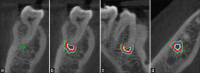

Figure 1

(a) Mask of the segmented periapical lesion in the coronal slice. Masks of lesion border (yellow), bone 0.0–0.5 mm (blue), 0.51–1.0 mm (red), 1.01–1.5 mm (purple), and 1.51–2.0 mm (green) peripheral to the lesion for radiodensity measurements in (b) coronal, (c) sagittal, and (d) axial slices